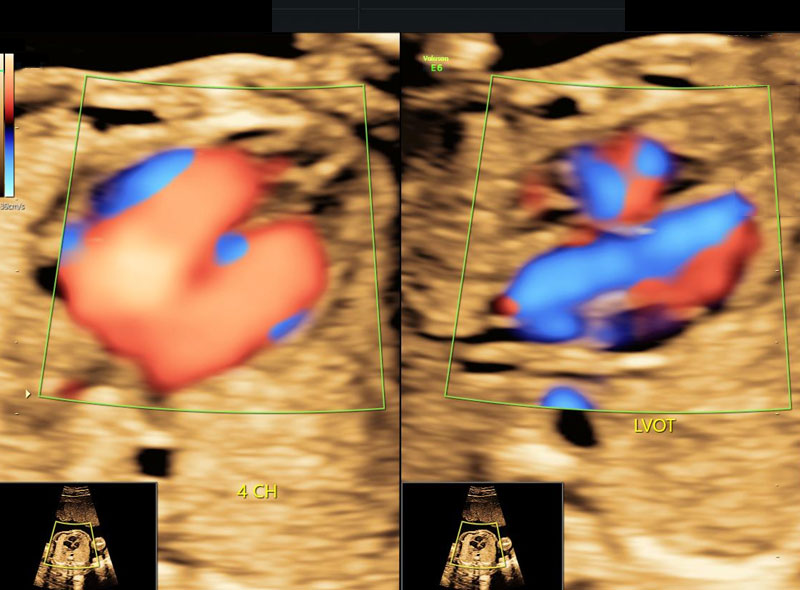

It is usually done at 19-20 weeks of pregnancy in every patient irrespective of prior scans. Doctors will study the baby’s structure in great detail and will be able to determine whether baby’s growth is on track. They will be able to pick up structural problems like heart defects, spine defects, brain defects etc. Not all findings highlighted in the scan, will need action. Many of these will only need a follow up and will be associated with normal outcomes. Some will need further testing - like amniocentesis to rule out genetic problems/infections etc. Unfortunately, some will be severe enough so that family is offered the option of termination of pregnancy. In our country this option is available till 24 weeks of pregnancy.